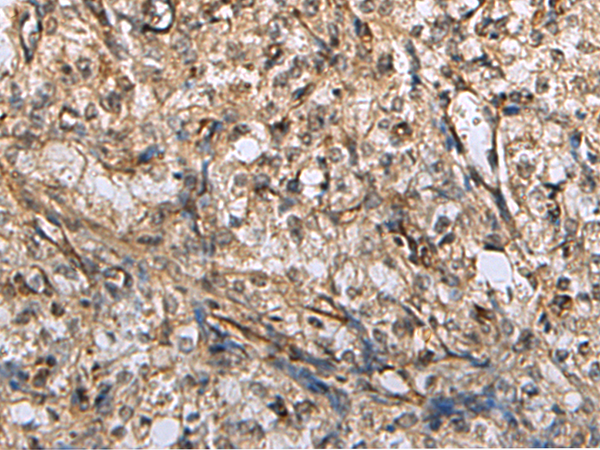

IHC positive control: |

Human brain |

IHC Recommend dilution: |

50-200 |